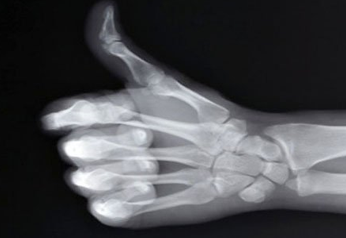

뼈는 우리 몸의 기초이며, 균형과 안정을 유지하고, 다양한 영양소를 저장하는 우리 몸의 필수적인 부분입니다. 뼈 건강을 관리하는 것은 전반적인 건강에 긍정적인 영향을 미치므로 뼈 건강에 좋은 음식을 자주 먹고 뼈 건강에 좋은 습관을 갖는 것이 좋습니다. 그럼 이번에는 뼈 건강에 좋은 음식과 습관에 대해서 한번 알아보겠습니다.